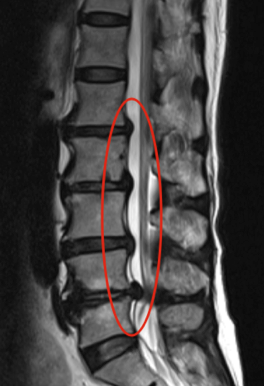

Przepuklina krążka kręgowego polega na wyjściu jego zawartości, czyli jądra miażdżystego, przez szczelinę we włóknistej powłoce krążka (ryc. 2).

Ryc. 2